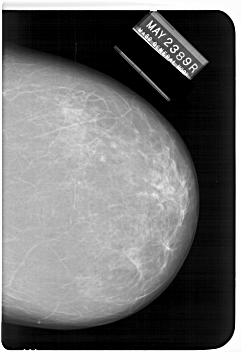

A_1247_1.RIGHT_MLO

RIGHT_CC LINES 6811 PIXELS_PER_LINE 4561 BITS_PER_PIXEL 12 RESOLUTION 43.5 NON_OVERLAY

RIGHT_MLO LINES 6601 PIXELS_PER_LINE 4591 BITS_PER_PIXEL 12 RESOLUTION 43.5 NON_OVERLAY